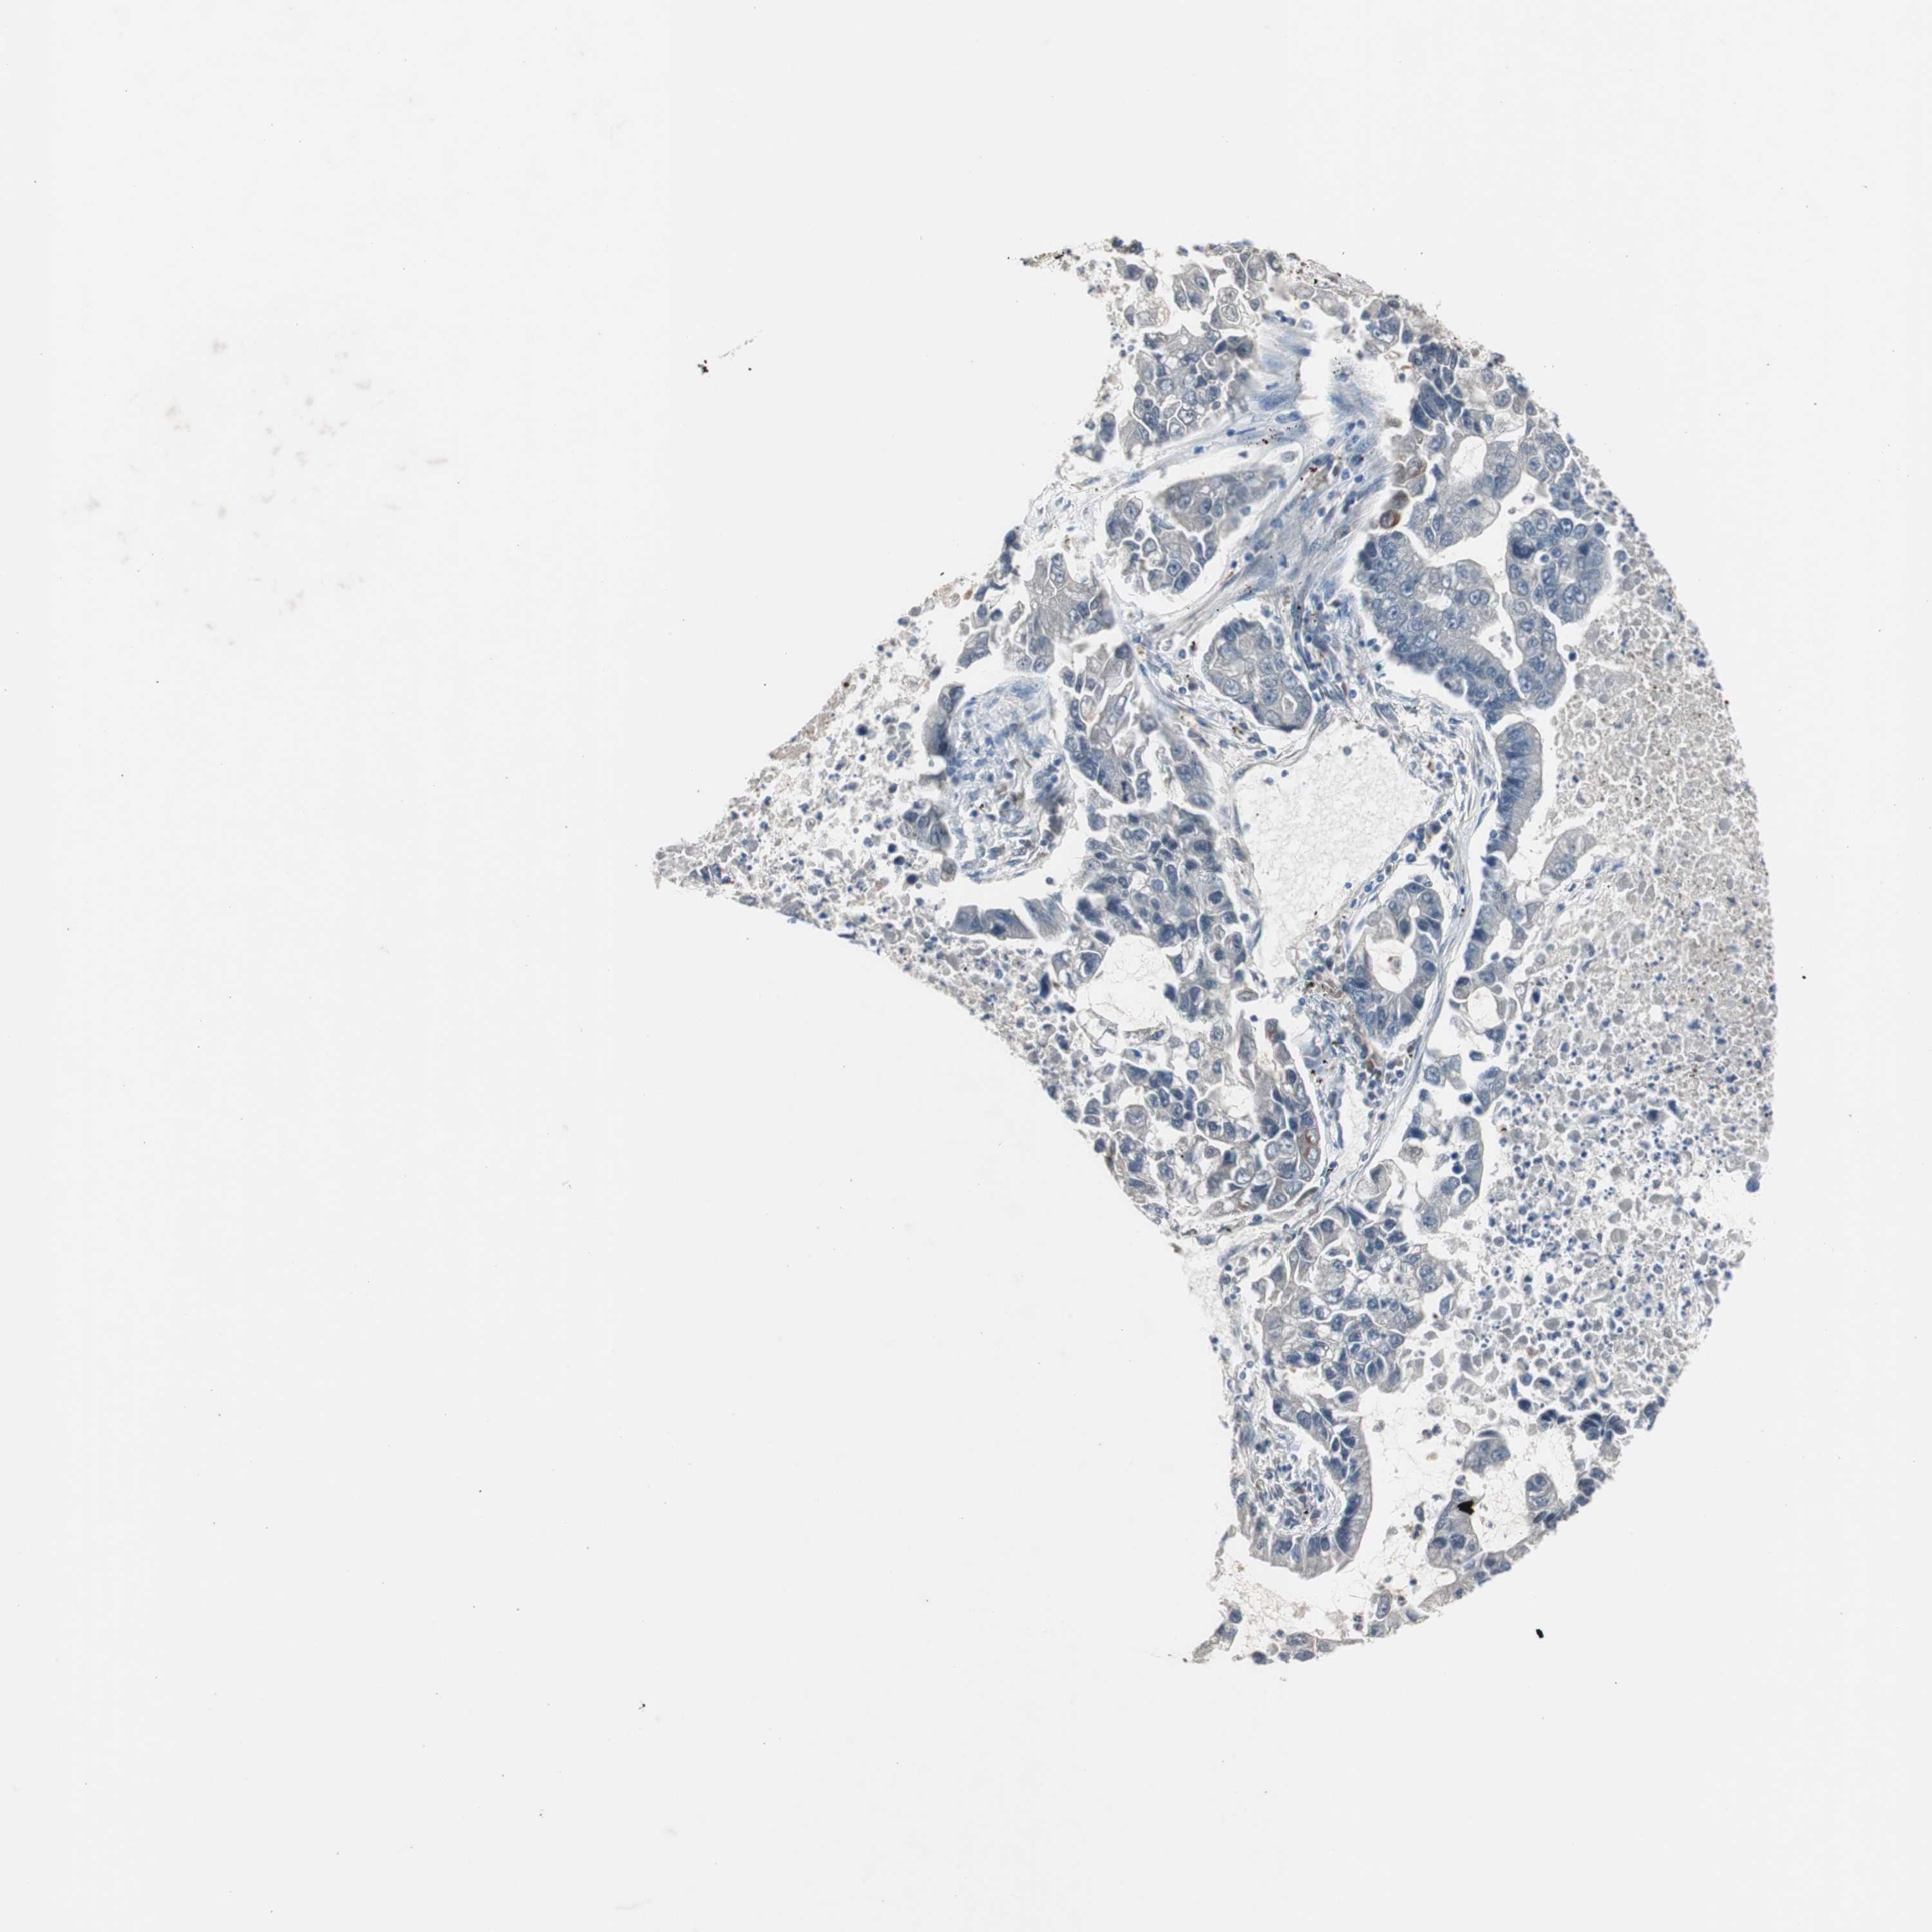

LUNG ADENOCARCINOMA (VALIDATION) - Interactive survival scatter ploti

The Survival Scatter plot shows the clinical status (i.e. dead or alive) for all individuals in the patient cohort, based on the same data that underlies the corresponding Kaplan-Meier plots. Patients that are alive at last time for follow-up are shown in blue and patients who have died during the study are shown in red.

The x-axis shows the expression levels (FPKM) of the investigated gene in the tumor tissue at the time of diagnosis. The y-axis shows the follow-up time after diagnosis (years). Both axes are complimented with kernel density curves demonstrating the data density over the axes. The top density plot shows the expression levels (FPKM) distribution among dead (red) and alive patients (blue). The right density plot shows the data density of the survived years of dead patients with high and low expression levels respectively, stratified using the cutoff indicated by the vertical dashed line through the Survival Scatter plot. This cutoff is automatically defined based on the FPKM cutoff that minimizes the p-score. The cutoff can be changed by dragging the vertical line or by entering a cutoff value in the square labeled "Current cut-off".

Under the Survival Scatter plot the p-score landscape (black curve; left axis) is shown together with dead median separation (red curve; right axis). Dead median separation is the difference in median mRNA expression between patients who have died with high and low expression, respectively. It is calculated as follows: median FPKM expression of dead patients with high expression - median FPKM expression of dead patients with low expression. This is intended to aid the user in visually exploring custom cutoffs and the associated p-scores and dead median separation.

Individual patient data is displayed and can be filtered by clicking on one or more of the category buttons on the top of the page. Categories describing expression level and patient information include: high, low, alive, dead, female, male and tumor stages. The scale of the x-axis can be toggled between linear and log-scale by clicking on the "x log" button. Mouse-over function shows TCGA ID, patient information and mRNA expression (FPKM) for each patient.

& Survival analysisi

Kaplan-Meier plots summarize results from analysis of correlation between mRNA expression level and patient survival. Patients were divided based on level of expression into one of the two groups "low" (under cut off) or "high" (over cut off). X-axis shows time for survival (years) and y-axis shows the probability of survival, where 1.0 corresponds to 100 percent.

SERPINF1 is not prognostic in Lung Adenocarcinoma (validation)

Best expression cut offi

Based on the FPKM value of each gene, patients were classified into two groups and association between prognosis (survival) and gene expression (FPKM) was examined. The best expression cut-off refers the FPKM value that yields maximal difference with regard to survival between the two groups at the lowest log-rank P-value. Best expression cut-off was selected based on survival analysis .

When clicking on this number, the vertical dashed line indicating cut-off, the interactive survival plot, and the Kaplan-Meier curve will be adjusted to show results based on the best expression cut-off.

: 74.28

P scorei

Log-rank P value for Kaplan-Meier plot showing results from analysis of correlation between mRNA expression level and patient survival.

N/A

TCGA RNA samplesi

RNA-seq data is reported as average FPKM (number Fragments Per Kilobase of exon per Million reads), generated by the The Cancer Genome Atlas (TCGA) .

Normal distribution across the dataset is visualized with box plots, shown as median and 25th and 75th percentiles. Points are displayed as outliers if they are above or below 1.5 times the interquartile range. FPKM values of the individual samples are presented next to the box plot.

Average pTPM 157.6

Number of samples 105